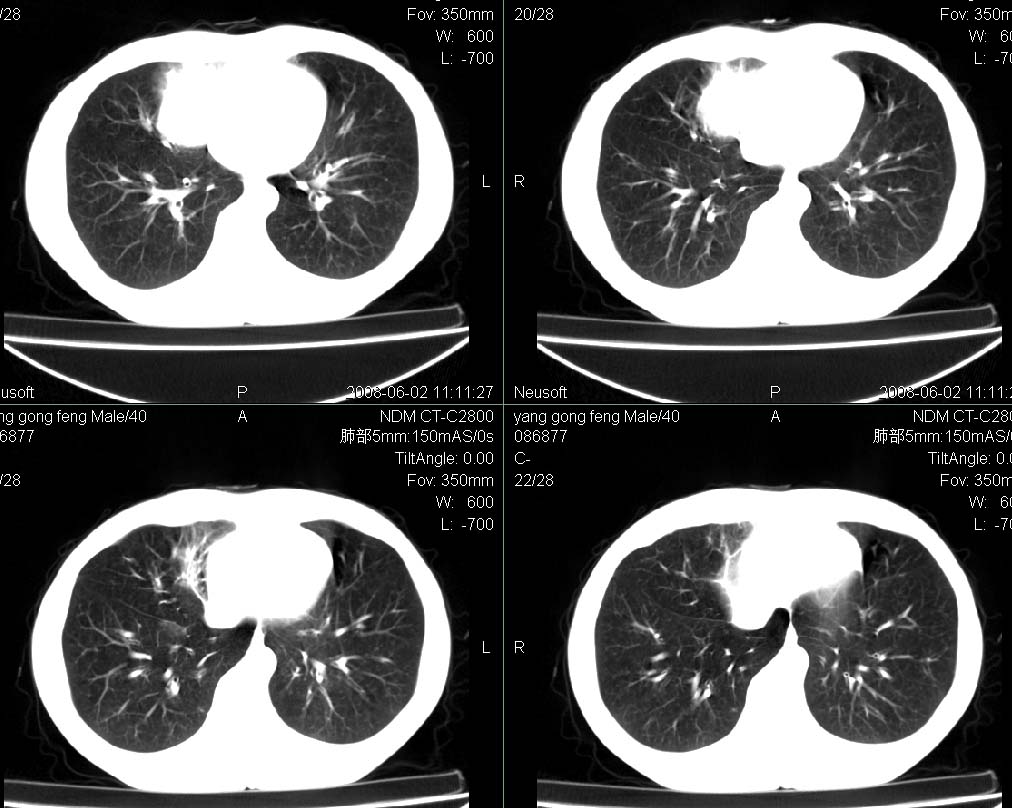

标题: CT15138:男,40,咳嗽胸痛. [打印本页]

标题: CT15138:男,40,咳嗽胸痛.

外院穿刺未见癌细泡,结核菌素实验阳性,未正规治疗2个月复查病灶及纵隔淋巴结增大

结合病史及临床表现考虑右侧中心型肺癌纵隔转移,

考虑周围型肺癌可能性大

右侧中心型肺癌纵隔转移!

右肺中叶肺癌,纵隔淋巴结转移.

考虑   右肺中叶肺癌,纵隔淋巴结转移.建议穿刺活检。炎性假瘤待排

考虑右肺中叶周围型肺癌并纵隔淋巴结转移。